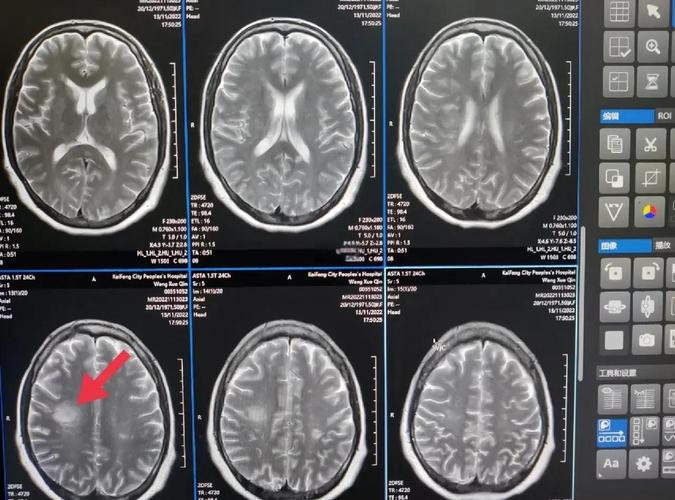

进行更高级的影像学检查——头颅MRI(磁共振)

- MRI是诊断早期脑梗死的“金标准”,它对水分子的变化非常敏感,在发病后1-2小时甚至更早就能发现缺血病灶。

- DWI序列(弥散加权成像):是MRI中诊断早期脑梗最关键的序列,发病后几分钟就能显示高信号梗死灶,几乎不受“时间窗”的限制。

- 如果高度怀疑脑梗但CT正常,医生会立即安排头颅MRI检查来确诊。